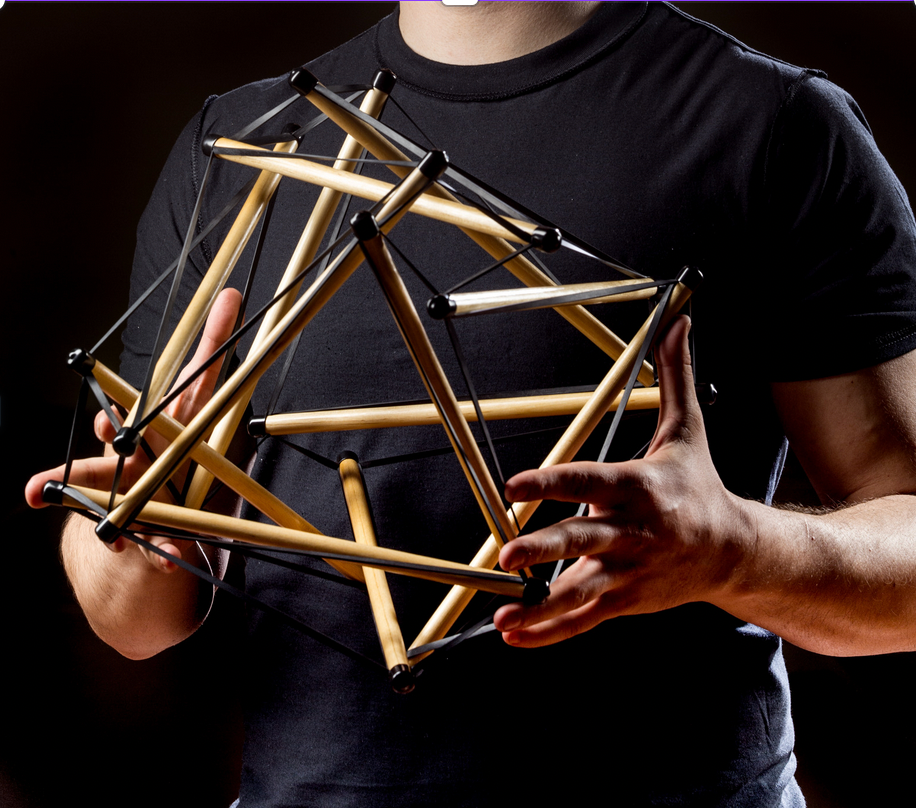

EL CUERPO HUMANO COMO MODELO DE TENSEGRIDAD

Se considera un sistema de tensegridad si dicho sistema se encuentra en un estado de autoequilibrio estable, formado por elementos que soportan compresión y elementos que soportan tracción

Se considera que los huesos son componentes de compresión discontinuos que se encuentran “flotando” en un tejido de tensión continua de las partes blandas, por lo tanto podemos interpretar el cuerpo humano desde la perspectiva de un SISTEMA DE TENSEGRIDAD.

Dicho de otro modo, el concepto de tensegridad describe cómo el cuerpo humano mantiene su estructura y función a través de una distribución equilibrada de tensiones y compresiones. En el sistema musculoesquelético, los músculos, fascias y el resto de tejidos blandos pueden generar tensión, mientras que los huesos actúan como elementos compresivos pudiendo soportar la compresión de las cargas. Esta interacción permite la estabilidad dinámica o en movimiento y la adaptación del cuerpo a las fuerzas externas.

NEURODINÁMICA Y SU RELACIÓN CON LA TENSEGRIDAD

Los nervios están integrados dentro del sistema fascial y su movilidad depende de la continuidad mecánica de todo el sistema de tensegridad. Esto implica que:

-Tensión equilibrada en la fascia = mejor deslizamiento neural

- La fascia actúa como un medio de transmisión de fuerzas y tiene conexiones directas con los nervios. Si la tensegridad del sistema fascial está alterada (por restricciones, adherencias o tensiones anormales), la movilidad neural se ve comprometida.

-Las restricciones en la red de tensegridad pueden generar disfunciones neurodinámicas

- Un bloqueo en un punto de la estructura fascial (por cicatrices, alteraciones posturales o restricciones articulares) puede afectar la capacidad del nervio para deslizarse dentro de su "túnel" anatómico. Esto puede generar síntomas como hormigueo, dolor neuropático o alteraciones motoras.

-Los nervios como estructuras tensiles dentro de la tensegridad

- Los nervios no solo se deslizan, sino que también responden a tensiones distribuidas en todo el sistema. Si hay una falta de movilidad en una zona, el nervio se verá sometido a mayor estrés en otro punto de su recorrido.

Por lo tanto, La movilización neurodinámica actua como reguladora de la tensegridad

Los ejercicios de neurodinámica permiten restaurar la movilidad normal de los nervios y al hacerlo, mejoran la distribución de cargas y tensiones en todo el sistema. Esto es clave en patologías como el síndrome del túnel carpiano, la ciatalgia o la neuralgia cervicobraquial.

En la práctica, podemos evaluar la movilidad neurodinámica considerando las cadenas fasciales y la tensegridad global:

- Si un paciente tiene ciática, además del test neurodinámico del SLR (Straight Leg Raise), podemos explorar restricciones en la fascia toracolumbar y la mecánica del pie.

- En un síndrome del túnel carpiano, además de la movilización del nervio mediano, evaluar la tensión en la fascia cervical y torácica puede mejorar el cuadro clínico.

La clave es integrar estos enfoques para abordar el cuerpo como un sistema interconectado, no solo como estructuras aisladas.